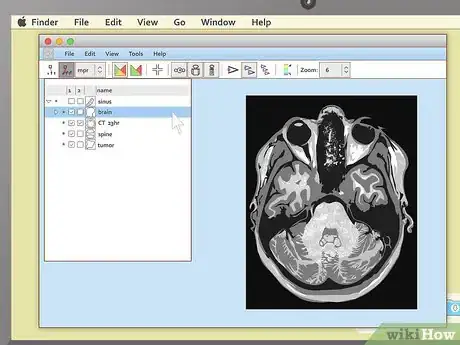

4Load the study. Again, the exact steps you'll need to take here can vary slightly depending on the exact program you have packaged with your images. Generally, most MRI viewers will have some sort of option to load or import images that you can select from the menu bar at the top of the screen. In this case, select this option, then pick the image file on your disc that you'd like to look at.

- Note that most medical imaging software refers to collections of images as "studies". You may not see an "import image" option, but you'll probably see something to the effect of "import study."

- Another option you may encounter is that, as soon as the program loads, it will present you with a "table of contents" of all the MRIs on the disc. In this case, simply select the study you want to view first to proceed.